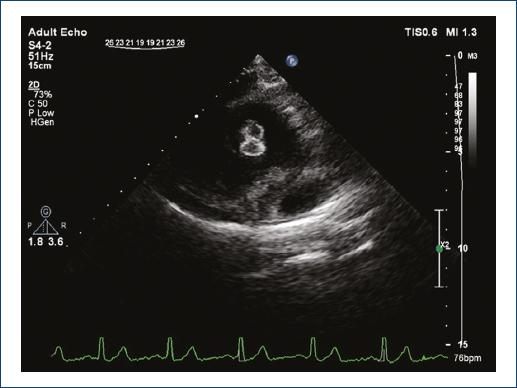

A 25-year-old woman presented to our echocardiography laboratory for a follow-up imaging study. She had a history of muscular ventricular septal defect (VSD) closure by Amplatzer Muscular VSD Occluder (St. Jude Medical, USA) 4 years before this visit. Since this repair, she has remained asymptomatic and was on no medication. In transthoracic echocardiography, the double disc device was visualized in apical four-chamber view (Fig. 1) with no residual VSD flow. Interestingly, in off-axis view of parasternal long-axis imaging, the device was visualized in the form of two side-by-side figure of 8 “Clover-leaf” appearances (Figs. 2 and 3).

Figure 2/Video 2 Off-axis parasternal long-axis view showing the figure of 8 image artifact of the occluder device.

Percutaneous disc occluders due to their specific “epitrochoidal” mesh configuration and the interaction with ultrasound waves; form this image artifact when viewed from a coronal imaging position1. Transthoracic echocardiography is the main method of follow-up for post-procedural device position, and accurate interpretation of views is of utmost importance2.

By increasing utilization of percutaneous closure devices for various indications including atrial and VSD, left atrial appendage, patent foramen ovale, recognition of this particular pattern as a normal imaging artifact of a deployed double-disc device when visualized from a coronal imaging position is necessary to avoid misinterpretations of studies such as malposition or displaced device.